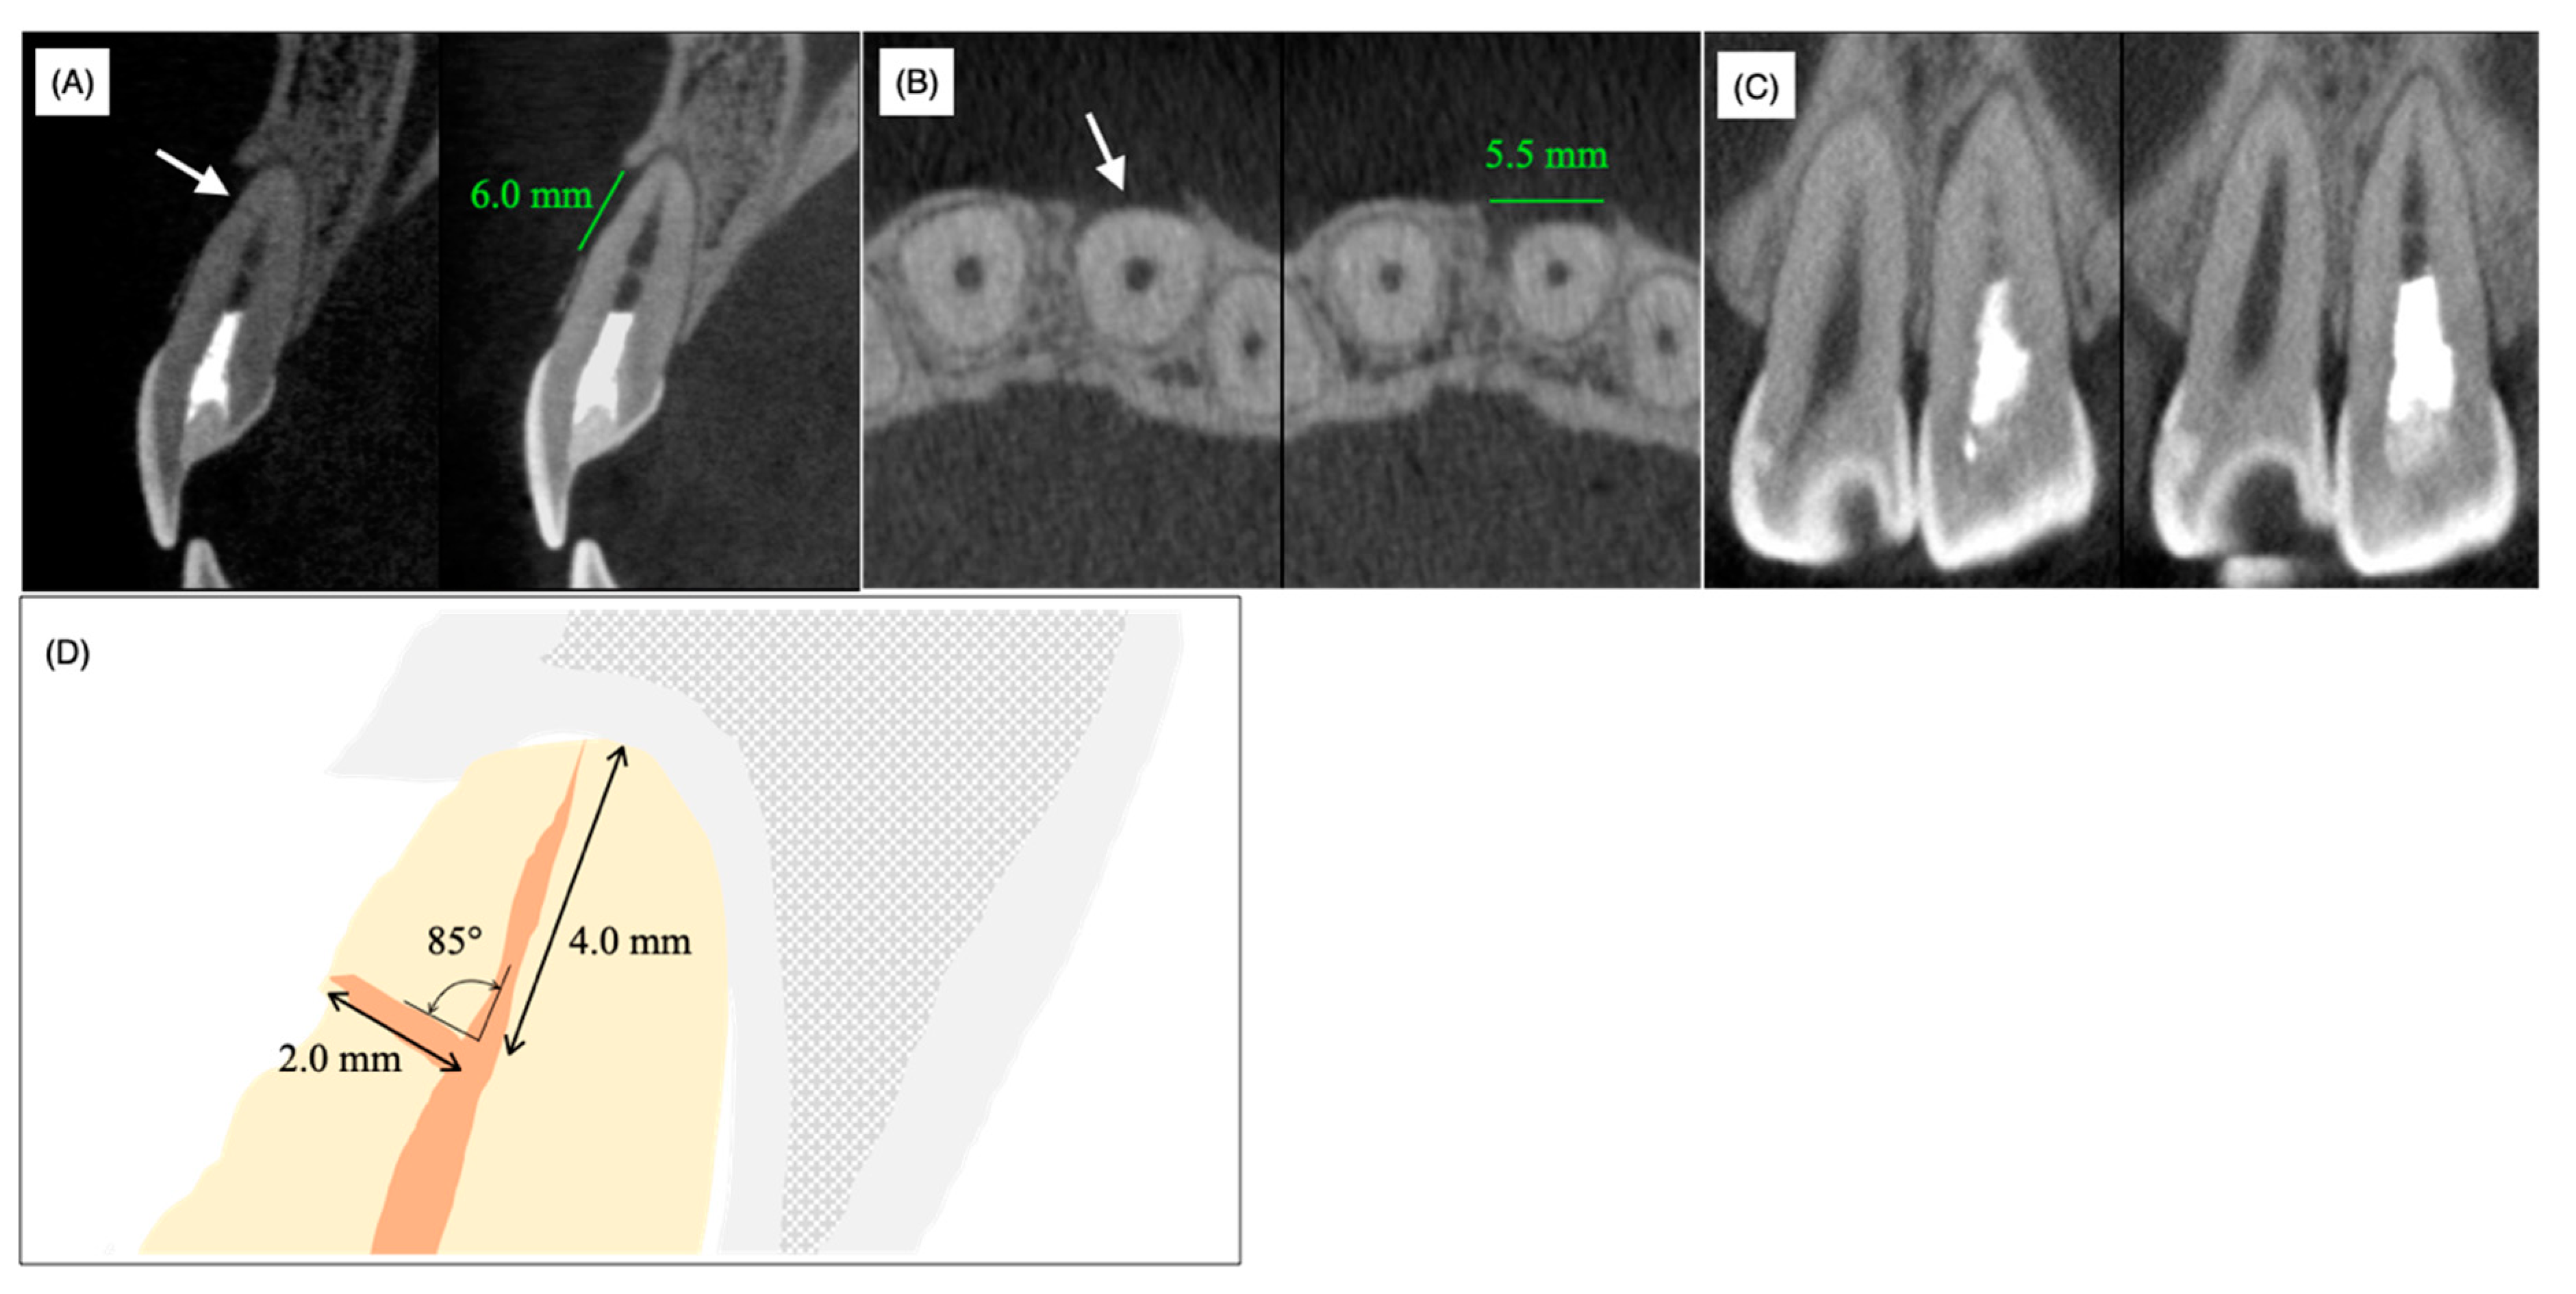

Cone-beam computed tomography (CBCT) demonstrated a horizontal accessory canal at the labial side of the root in the sagittal section (Figure 3A, arrow), bone resorption (length = 6 mm, width = 5.5 mm) whose center was positioned at the foramen of the horizontal accessory canal on the horizontal section (Figure 3B, arrow) and local enlargement of the periodontal ligament space on the mesial side of the middle part of the root (Figure 3C). In contrast to the labial and medial sides of the middle part of the root, the bone surrounding the apical apex was not resorbed and labial bone resorption did not reach the apical apex (Figure 3A,C). A schematic view of the periapical region based on CBCT analyses showed 4.0 mm and 2.0 mm distances from the anatomical apex to the orifice of the laterally localized accessory root canal and from the foramen to the orifice of the laterally localized accessory root canal, respectively; the angle between the main root canal and the laterally localized accessory root canal was 85°, which verified that the laterally localized accessory root canal occurred naturally rather than being caused by an iatrogenic perforation (Figure 3D).

As described above, 62.2% of maxillary central incisors have access to periodontal ligament tissue other than the apex foramen [1]. However, apical periodontitis mostly spreads from the apex, presumably because the diameter of the apex foramen is larger than that of the lateral foramen and ramifications [19,20]. Moreover, pulp tissue in accessory canals may survive and be immunologically resistant to bacterial invasion from the main root canal even when apical periodontitis with a radiolucent area is noted [20]. The average diameter of the main apical foramen in the maxillary frontal teeth is 0.28 mm according to Chapman et al. [21] and 0.31 mm according to Abdullah et al. [22]. Indeed, the apical foramen was narrow (Figure 1 and Figure 2) and a thin dentin bridge-like radiopaque white line was identified at the horizontal level of the lateral root foramen by CBCT analysis (Figure 3). Thus, we hypothesized that the pulp tissue in the apical region had calcification ability. As prolonged pulp inflammation is known to be related to pulp calcification such as the pulp stone [23] we assumed that the bacterial remnants from the primary carious treatment received at around 10 years of age induced chronic pulpal inflammation, which may have caused the calcification in the apical region. As we were unable to feel any dentin bridge-like hard tissue by hand during non-surgical endodontic treatment, this hard tissue was suggested to be fragile and flimsy.

Figure 3. Preoperative cone-beam computed tomography images (A) sagittal, (B) horizontal and (C) coronal. The arrow in (A) indicates the lateral foramen. (D) Schematic view of the sagittal section of the upper left incisor.